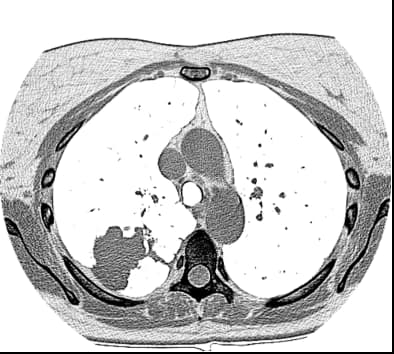

单击工具栏上的“标注测量”按钮,从标注测量下拉菜单中选择Length(或按L键),将光标放在起点上,然后按下鼠标左键并拖动鼠标以绘制长度测量的线段。松开按钮完成绘图。距离值将以毫米或像素显示。

从测量下拉菜单中选择角度(或按A键),按下鼠标左键并拖动鼠标以绘制角度的第一个手臂。释放按钮并移动鼠标以绘制第二只手臂。单击左侧按钮完成角度绘制。